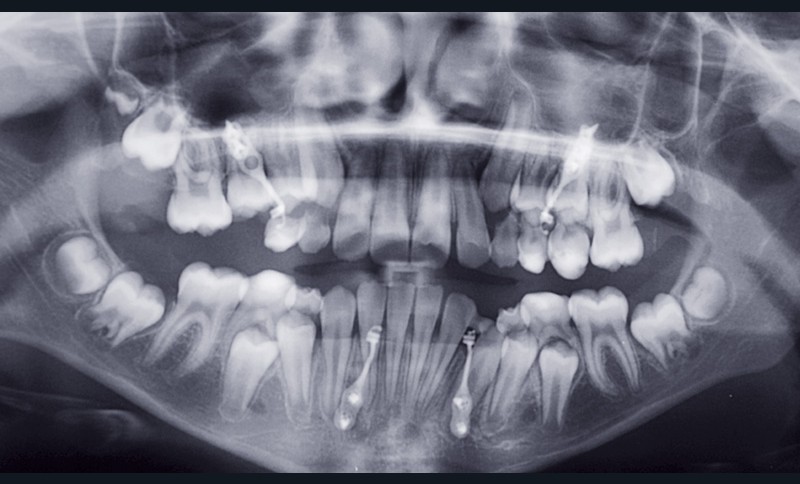

Après 6 mois d’orthopédie, la plaque au niveau du secteur I, qui a toujours été défaillante, devient mobile et finit par se débricoler. De ce fait, les élastiques du côté gauche ont davantage fonctionné ; il en résulte une déviation du milieu incisif mandibulaire à gauche (fig. 3).

Une nouvelle plaque a été fixée mais aussitôt reperdue. De ce fait, nous avons décidé de continuer avec une phase de finition multibague (fig. 4).